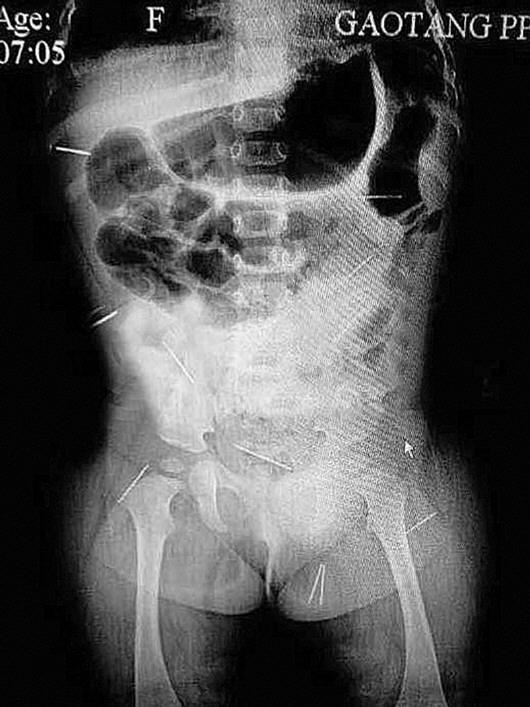

X光片显示,子萱体内有12根钢针。

■ 5根钢针靠近内脏

北京儿童医院的医生根据CT片,确定孩子腹部5根钢针靠近内脏,可能有危险,女婴将在医院急诊留观。

22日,小子萱被父亲和大伯带到北京儿童医院,急诊科主任和外科主任等专家进行初步检查后表示,12枚钢针已经进入体内近两个月,小子萱的情况在全国都比较罕见。